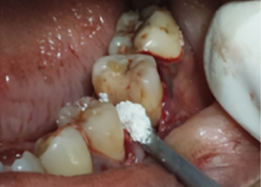

Bone Graft Placement

Placement of PRF Membrane